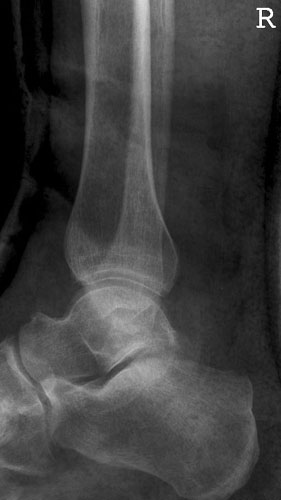

OSG seitlich

Fehler

Doppelkonturierung im oberen Teil der Talusrolle. Die Beurteilung des OSG ist nicht möglich. Die Spitze des Malleolus lateralis steht höher als die Spitze des inneren Malleolus.

Abhilfe

Der Fuß muss gesamthaft etwas höher gelagert werden, bei streng seitlicher Zentrierung.